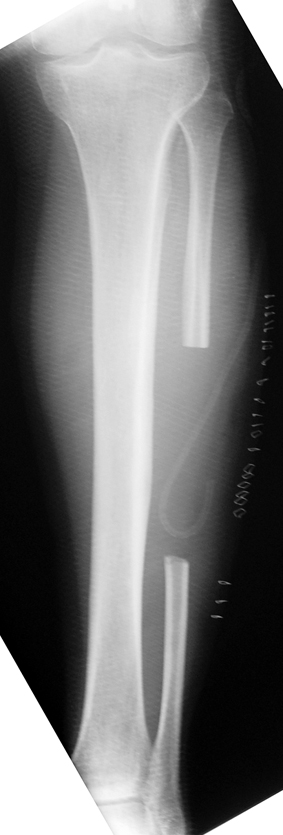

Uygun radikal debridman tüm nekrotik kemik ve yumuşak dokuların çıkartılmasını gerektirir, ve sıklıkla uzuvda instabiliteye neden olur. Kalan kemik ve yumuşak doku defektinin bir şekilde fiksasyonu ve rekonstrüksiyonu gereklidir. İlizarov’un ortaya koyduğu distraksiyon osteogenezi yöntemi, kaynamanın elde edilmesi, deformitenin düzeltilmesi, bacak boy eşitsizliğinin giderilmesi ve segmental defektlerin rekonstrükte edilmesi için başarıyla kullanılmaktadır.

Eksternal fiksatör ile geçen süre (eksternal fiksasyon indeksi), gereken distraksiyon miktarına bağlıdır ve bu süre boyunca bazı komplikasyonlarla karşılaşılabilir. Distraksiyon dönemi sona erdikten sonra, distraksiyon süresinin iki katını aşan konsolidasyon döneminde hastalar eksternal fiksatörü zorlukla tolere edebilirler. Yeterli konsolidasyon sağlanmadan eksternal fiksatör çıkartılırsa ise kırıklar, deformite ve kısalık oluşabilir. Hastanın fiksatör ile birlikte geçirdiği sürenin azaltılması ve böylece hasta konforunun ve aktivite düzeyinin arttırılması için intramedüller çivi üzerinden uzatma yöntemi uygulanmaktadır. Bu yöntemde distraksiyon dönemi sona erdiğinde kemiğin içindeki çivi statik olarak kilitlenmekte ve eksternal fiksatör çıkartılmaktadır. Stabilizasyon intramedüller çivi tarafından sağlandıktan sonra konsolidasyon dönemi gerçekleşmektedir. Bu şekilde hem eksternal fiksatörün uzun süre kalmasından hem de erken çıkartılmasından kaynaklanan komplikasyonların önüne geçilmektedir.